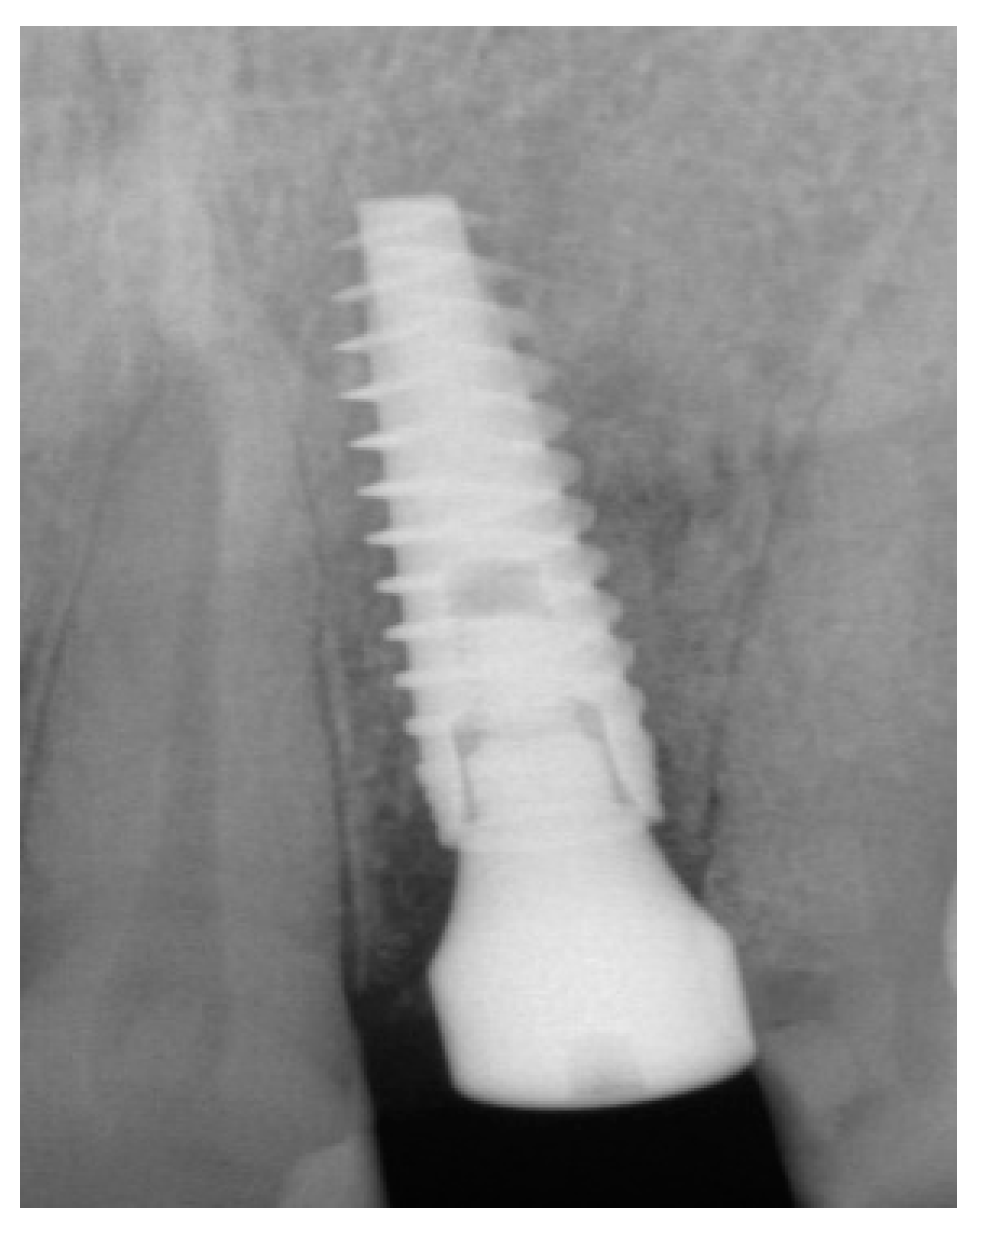

The surgical protocol was followed as described for the previous patient. Likewise, an implant was placed, followed by the placement of bone graft material over the defect and covered with a resorbable membrane. Six months later, the implant was fully intergraded (Figure 10), and the soft tissue appeared to be within normal limits (Figure 11). The implant was restored with a ceramic zirconia crown. Figure 12 presents the patient three years after treatment.

Figure 10.

Radiograph of the lateral incisor.